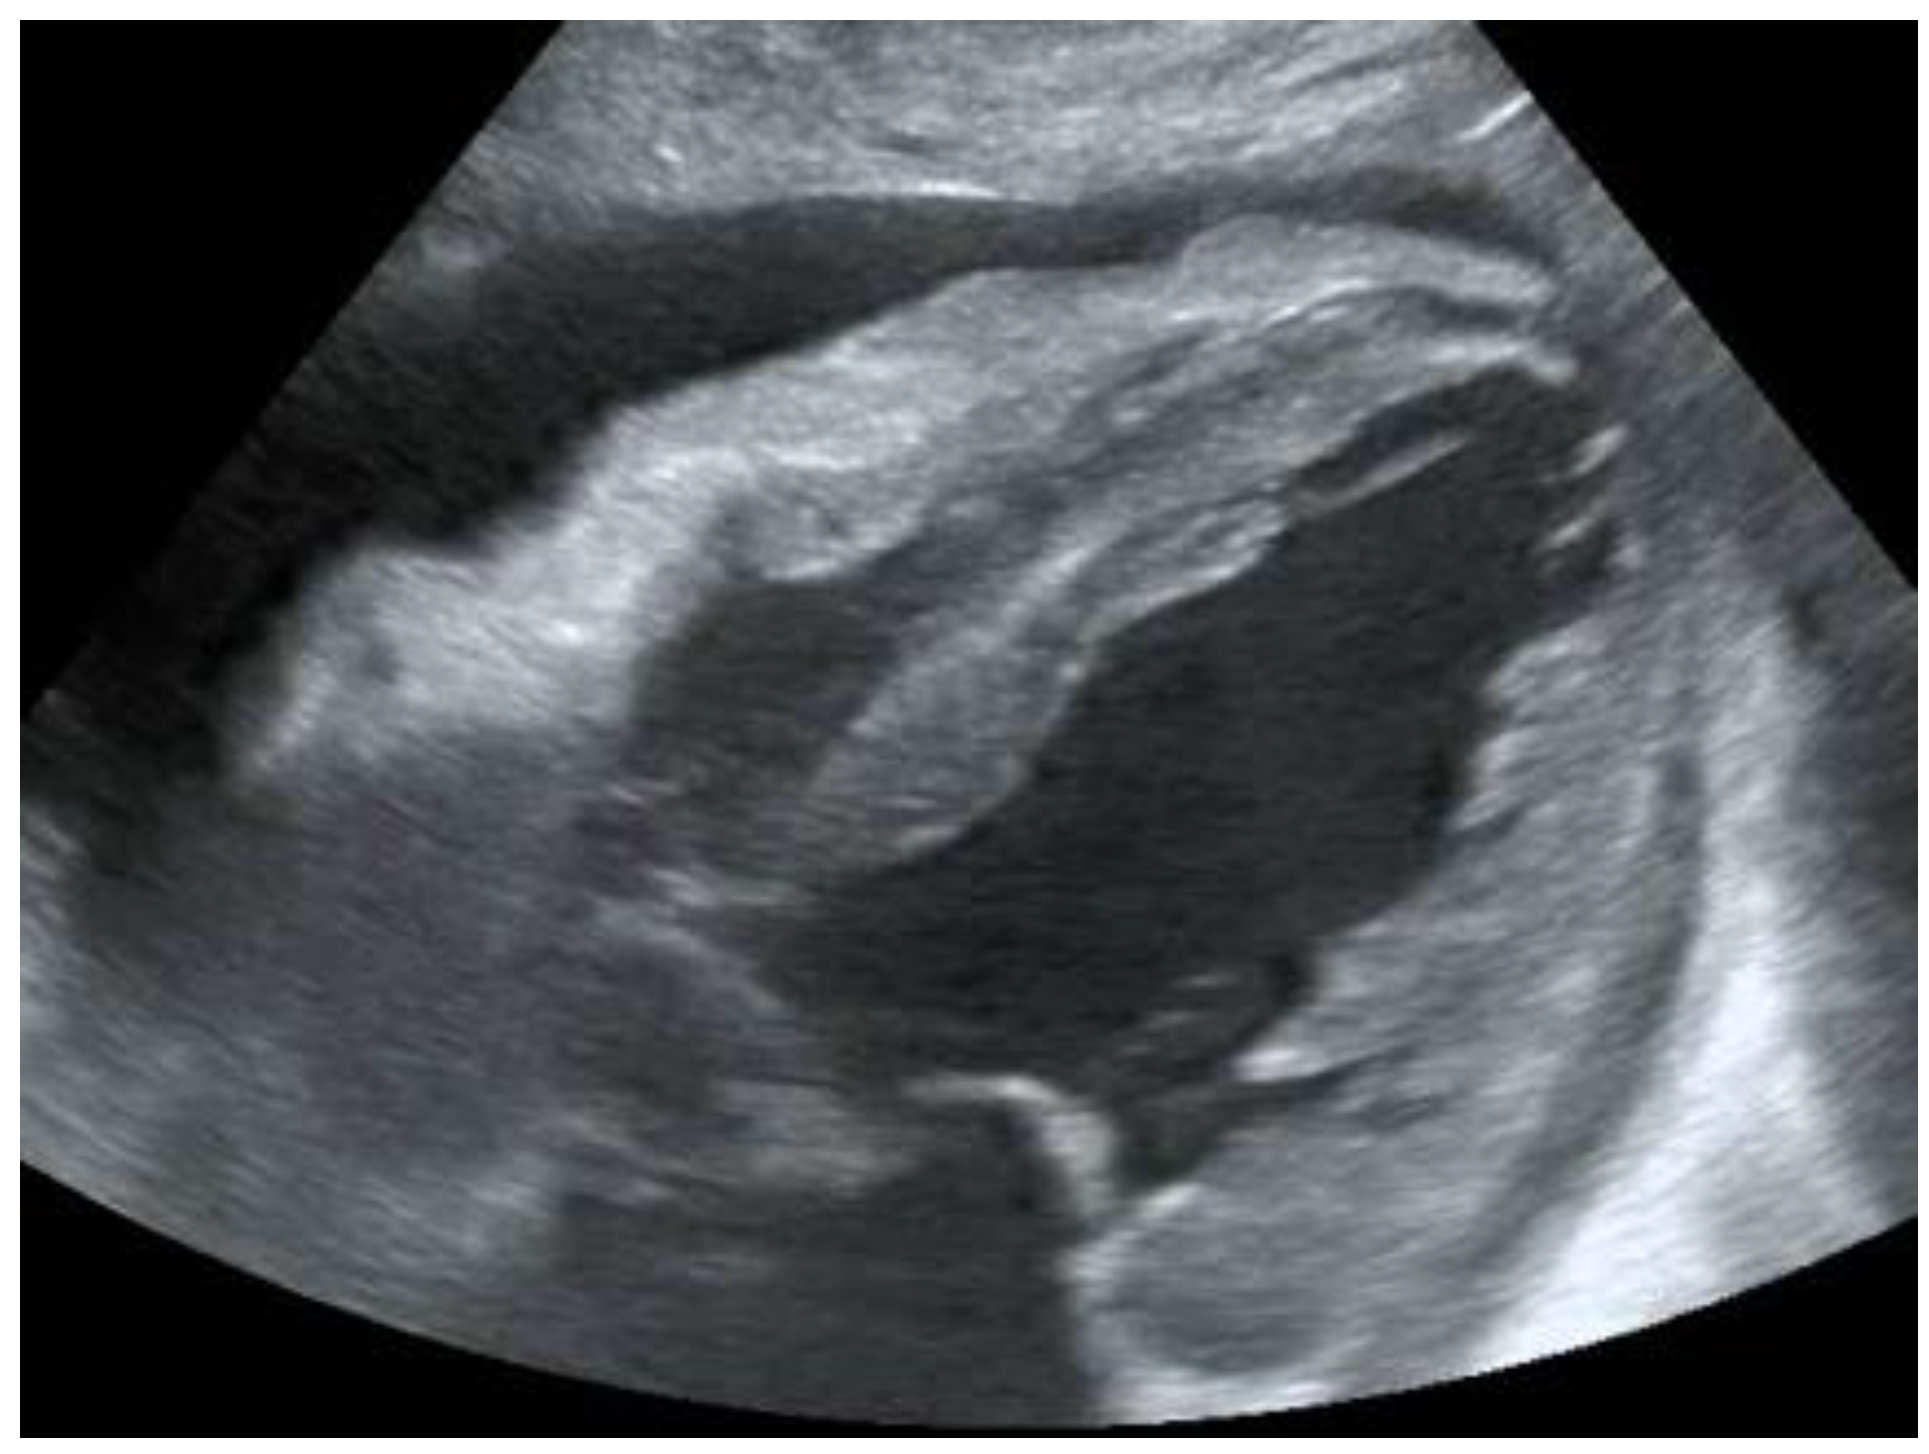

| Pleural effusion | Detection of hypoechoic material in the pleural cavity (Figure 7) |